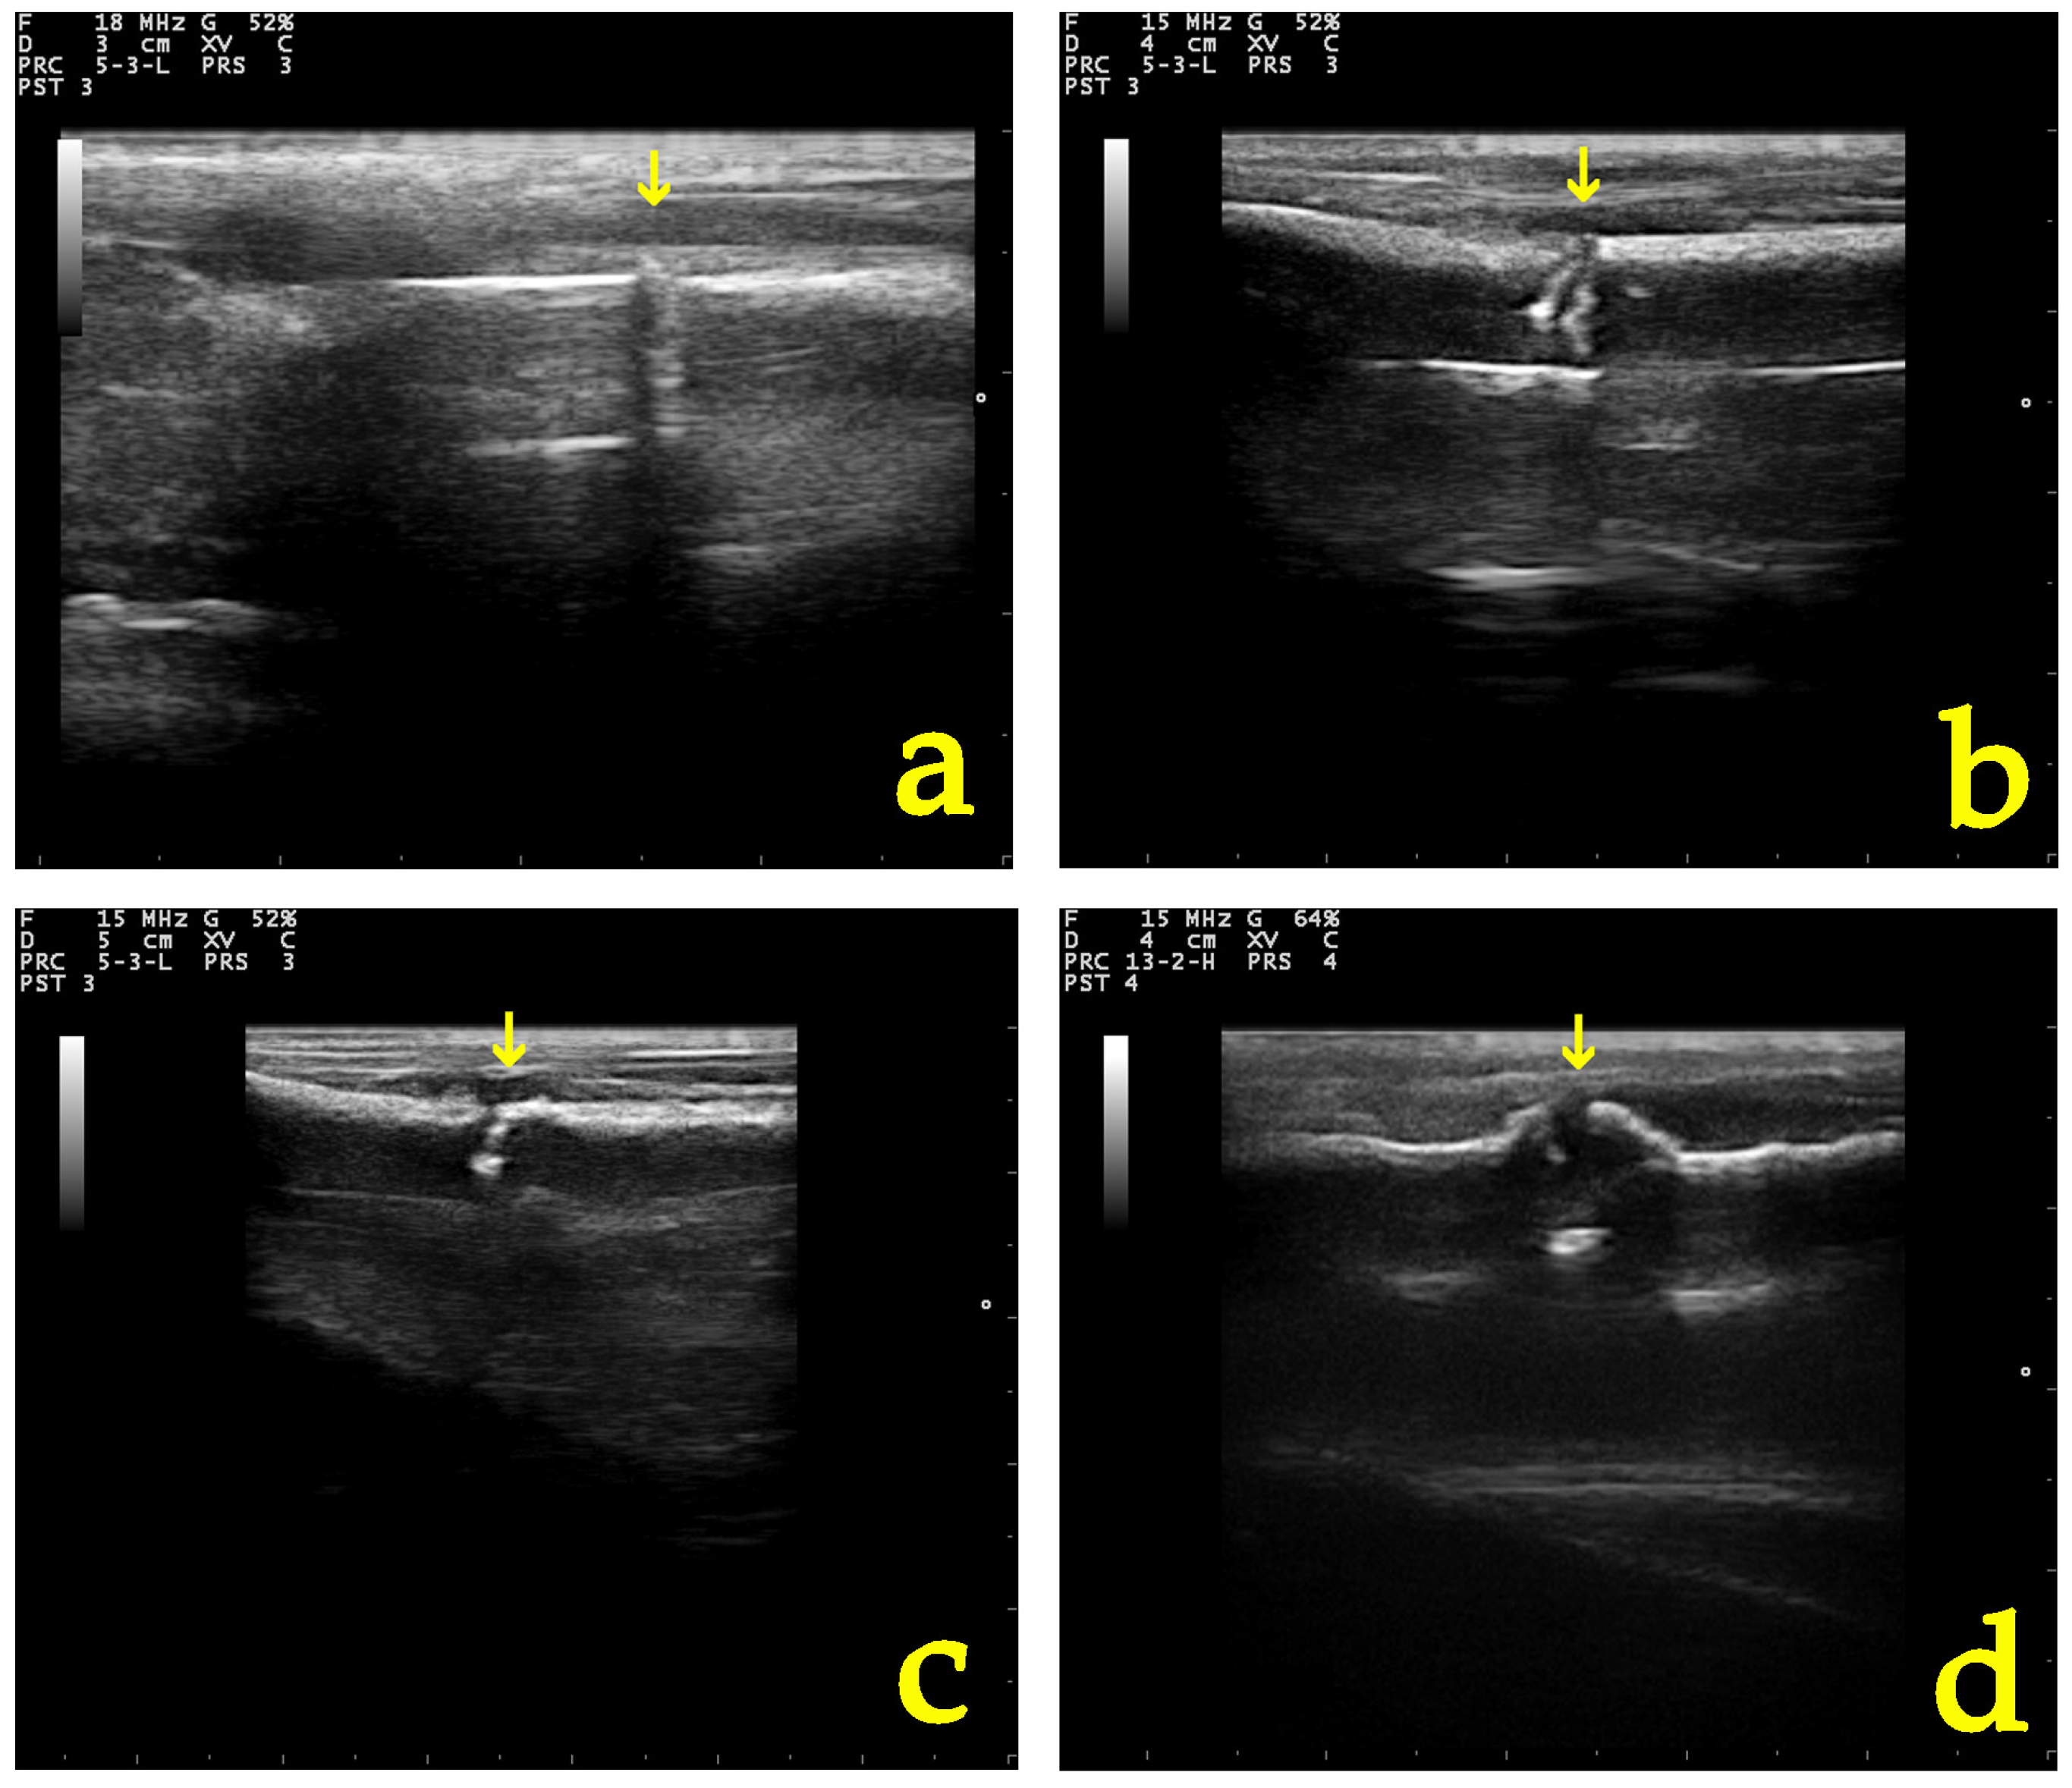

3.5.1. Ultrasonographic Examination

3.5.2. Radiographic Examination

| Parameter of Ultrasonographic Examination | Group | D0 | D5 | D10 | D20 | D28 |

|---|---|---|---|---|---|---|

| Echogenicity and structural organization of the tissue at the fracture site | A | 1 (1–1) | 2 (1–2) | 2 (2–2) | 3 (3–4) | 3.5 (3–4) |

| B | 1 (1–1) | 1 (1–2) | 2 (2–2) | 3 (2–4) | 4 (2–4) | |

| Formation of the callus and the vascularization present at the osteotomy | A | 1 (1–1) | 2 (2–2) | 2 (2–2) | 3 (2–4) | 3.5 (3–4) |

| B | 1 (1–1) | 2 (2–2) | 2 (1–2) | 3 (2–4) | 4 (2–4) | |

| Total grade | A | 1 (1–1) | 1.5 (1–2) | 2 (2–2) | 3 (3–4) | 3.5 (3–4) |

| B | 1 (1–1) | 1 (1–2) | 2 (2–2) | 3 (2–4) | 4 (2–4) |